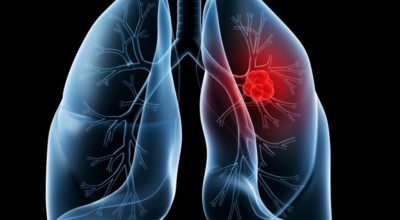

폐암에 대해서

폐에 발생된 악성 종양을 말하며 오랜 기간 흡연해온 남성들에서 발병률이 높고 요즘 들어 가지가지 환경적인 요인의 영향과 간접흡연으로 흡연하지 않는 여성에서도 많이 발생하고 있어요. 증상을 느껴 병원을 찾았을 때는 수술하기 늦은 경우가 많아 사망하는 비율이 매우 높은 암입니다.

폐 자체에서 생기거나 다른 장기에서 발생된 암이 폐로 전이되어 나타나기도 하고 특별한 초기 증상이 없는 경우가 많다고 하며 암이 진행된 후에도 일반적인 감기 증상인 기침과 가래 외의 특이 증상이 나타나지않아 증상만으로는 진단이 쉽지 않아요. 폐암 역시 다른 암들과 마찬가지로 조기 발견 및 치료가 매우 중요하므로 일상 속에서 폐암 초기증상을 간과하지 않도록 주의를 기울여야 해요.